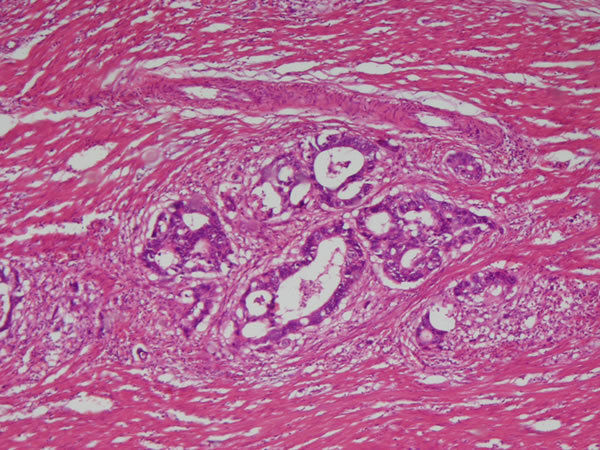

Intestino grosso - Epit. cilíndrico simples Inflamação crônica granulomatosa- granuloma por esquistossomose (form tumoral) Causas: Infecções persistentes, reação de hipersensibilidade, exp. agentes tóxicos |

Intestino grosso - epit cilindrico simples Infl. crônica granulomatosa granulomas são as partes mais eosinofílicas. pequeno aumento Causas: Infecções persistentes, reação de hipersensibilidade, exp. agentes tóxicos |